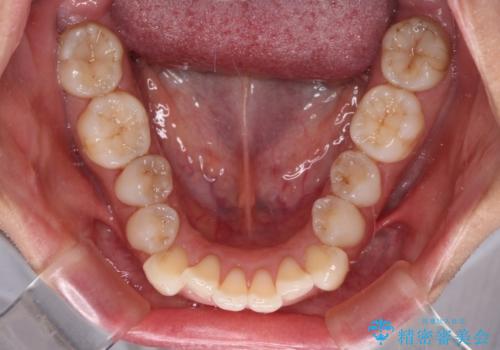

補助装置を用いて奥歯の咬み合わせを事前に改善 インビザラインによる矯正治療

歯列としてはインビザラインでもワイヤー矯正でも対応できるものでしたが、奥歯の咬み合わせを見た時に上顎がやや前方にあり、インビザライン単独では時間のかかってしまう可能性があるため、補助装置を治療当初に使用することで、インビザラインによる治療をスムーズに行えるように計画しました。

インビザラインは得意・不得意の差がはっきりとしているため、補助装置やワイヤー装置などをうまく活用することで、治療期間を短縮するとともに、より理想的な仕上がりを達成することができます。